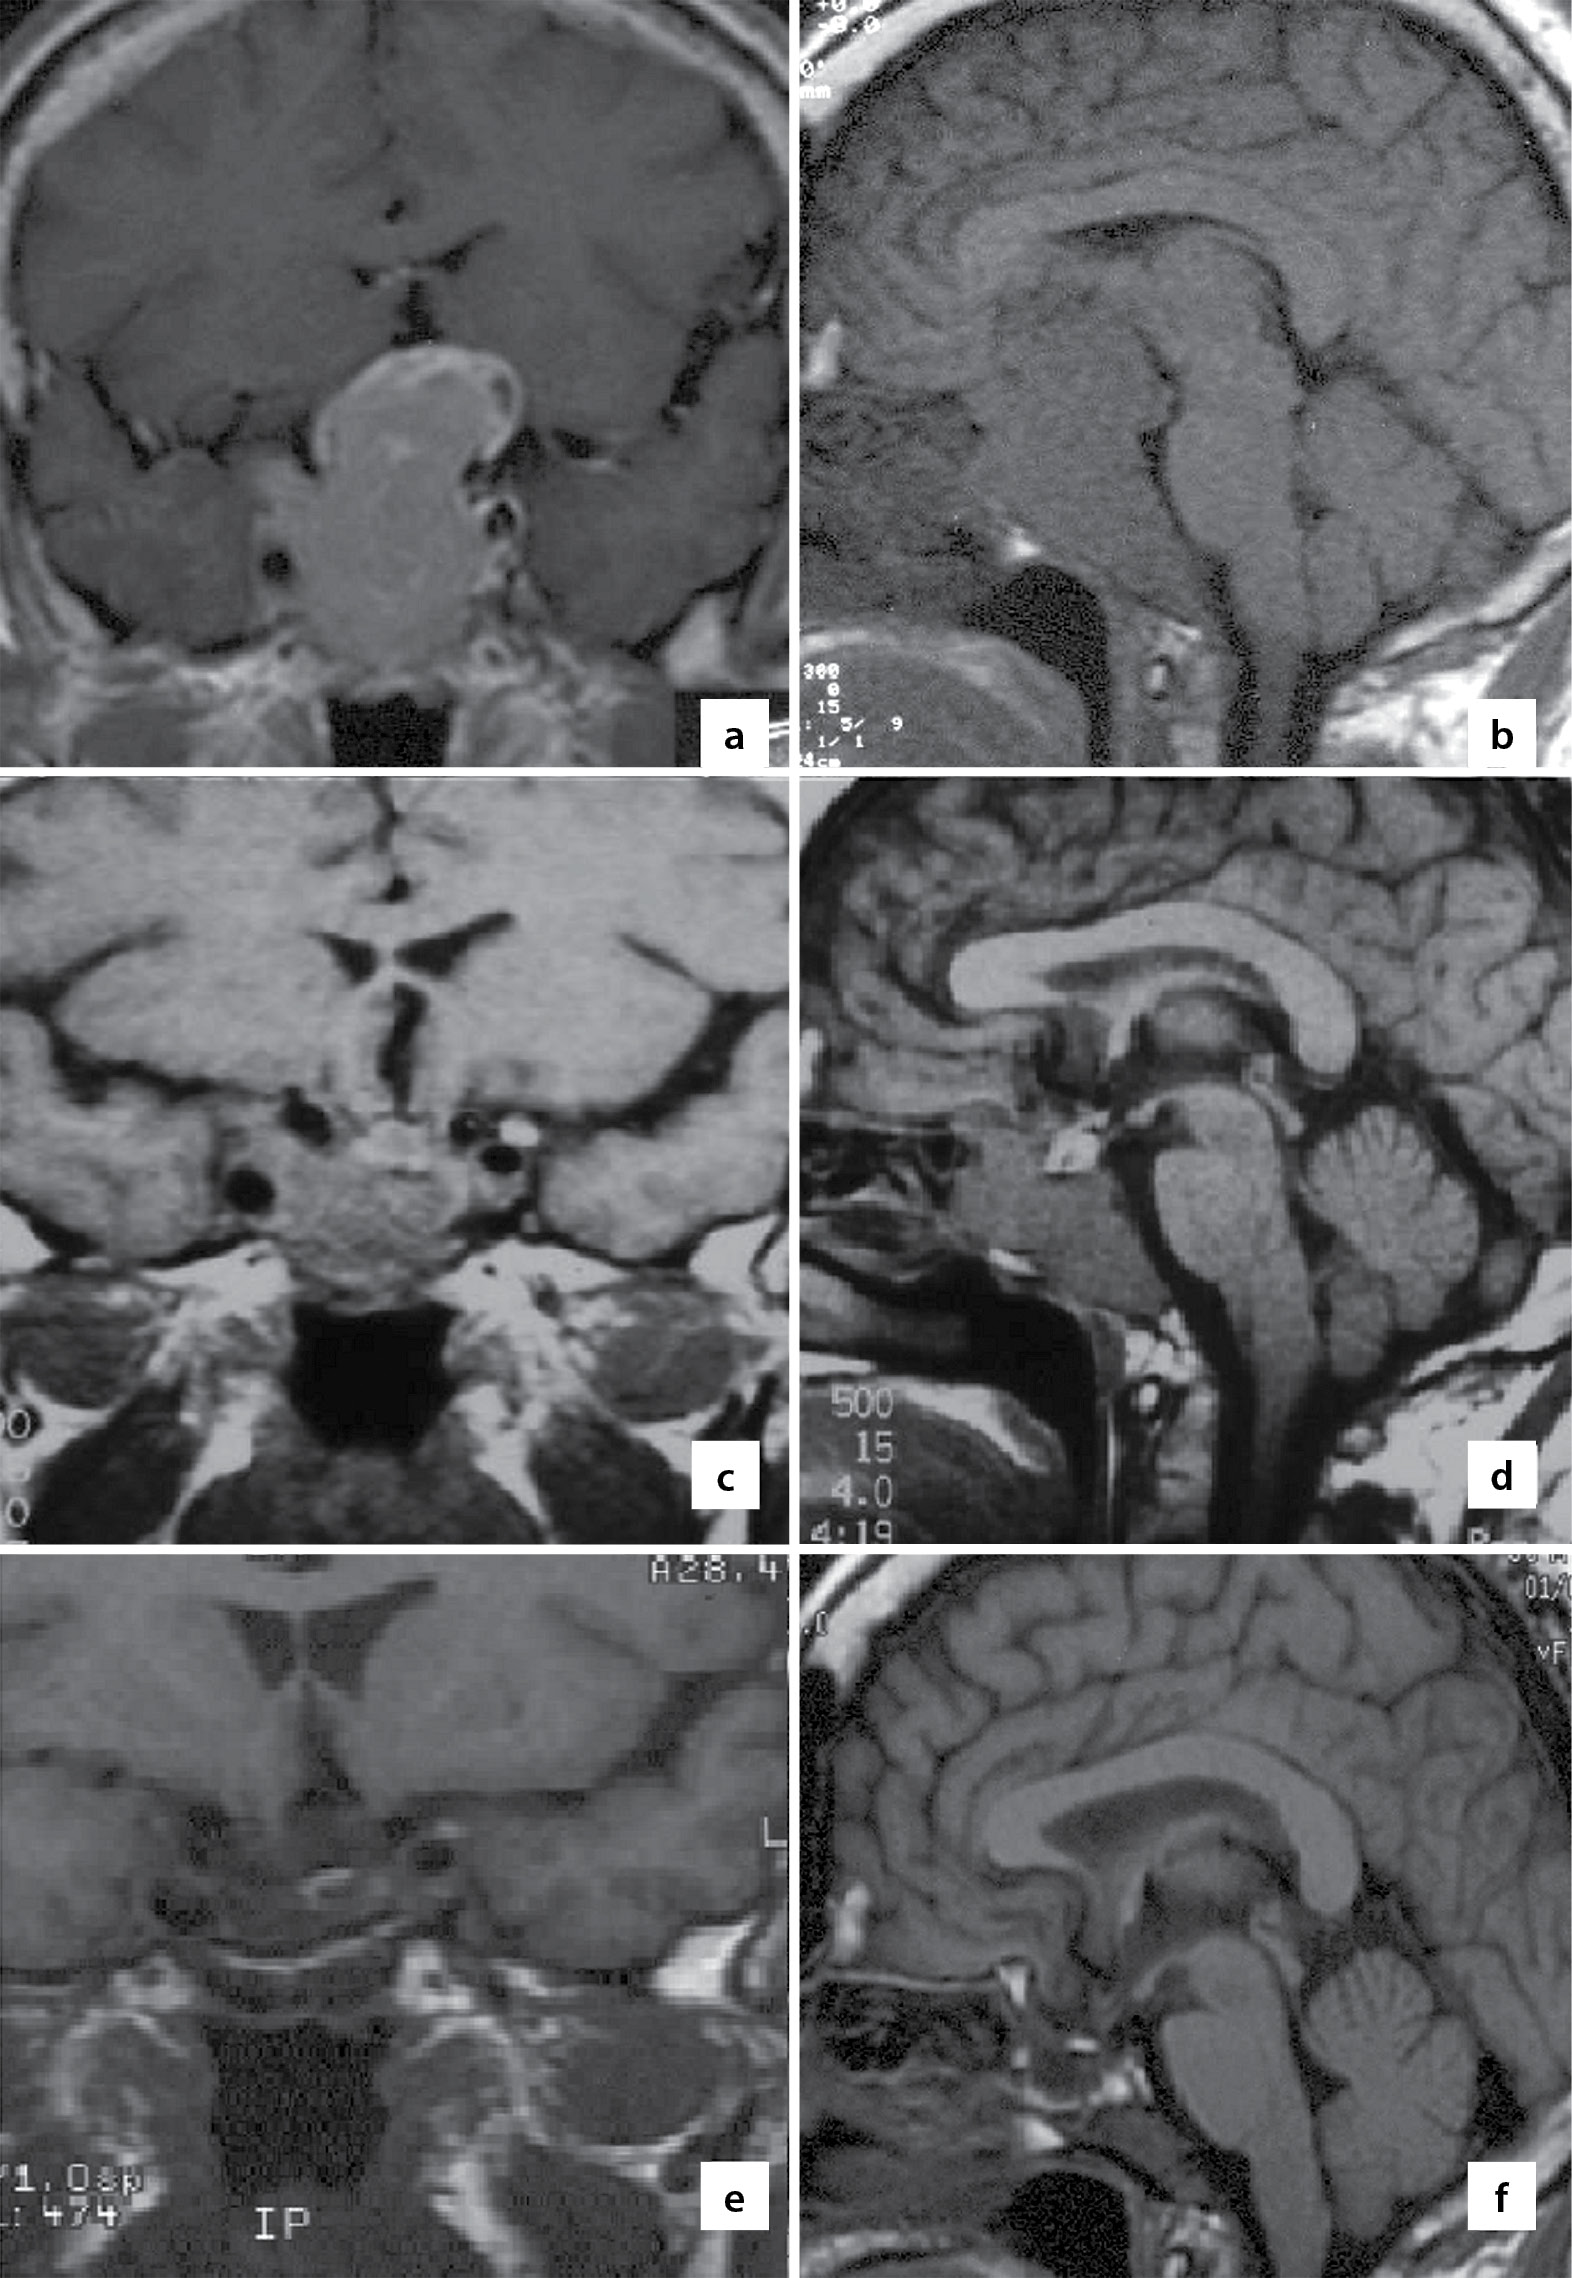

Амбулаторное обследование, проведенное в НМИЦН им. ак. Н.Н. Бурденко, позволило диагностировать опухоль эндо-супра-латеро-инфраселлярной локализации гигантских размеров, максимальный размер которой составил 6,7 см (рис. 1 a, b); зрительные нарушения в виде битемпоральной гемианопсии и снижение остроты зрения правого глаза (VIS ОD=0,4), VIS ОS=1,0, небольшой правосторонний экзофтальм в 1,5 мм (выстояние ОD=18 мм, ОS=16,5 мм). Уровень ПРЛ был более 5000 мЕд/л (30–360) (исследование с разведением сыворотки для определения ПРЛ не проводилось), тестостерона — 2,3 (8–35) нмоль/л, тиреотропного гормона — 1,3 (0,4–4,0) мЕд/л, св. Т4 — 12 (9–22) нмоль/л, кортизола — 398 (260–720) нмоль/л.

Рисунок 1. МРТ во фронтальной и сагиттальной проекциях.

a, b. Перед 1-м этапом хирургического лечения (удаление транскраниальным доступом). Визуализируется гигантская аденома гипофиза эндо-супра-латеро-инфраселлярной локализации.

c, d. Через 3 мес после удаления опухоли транскраниальным доступом и курса терапии каберголином перед 2-м этапом хирургического лечения (удаление транссфеноидальным доступом). Визуализируется остаток опухоли эндо-латеро-инфраселлярной локализации.

e, f. Через 10 лет после удаления опухоли на фоне терапии каберголином. Регресс опухоли и «пустое» турецкое седло.

При контрольном обследовании через 3 месяца регрессировал парез правого глазодвигательного нерва, однако сохранялась слепота на правый глаз. При МРТ-исследовании (рис. 1 c, d) определялся остаток опухоли эндо-инфраселлярной локализации.

После операции продолжена терапия каберголином в дозе 1,5 мг с последующим ее снижением до 0,25 мг в неделю, которая привела к стойкой нормопролактинемии, восстановлению андрогенного статуса и отсутствию рецидива опухоли в течение последующего 10-летнего периода наблюдения (рис. 1 e, f). Через 3 года после операции у жены пациента наступила беременность, закончившаяся рождением здорового ребенка.